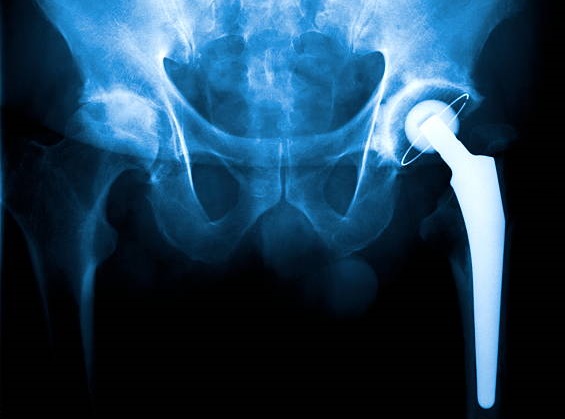

Hip Replacement Surgery: What Is It?

In hip replacement surgery, a physician removes a problematic hip joint and replaces it with an artificial joint (implant) to replace the worn-out bone and cartilage. Typically, metal, ceramic, and extremely hard plastic are used to make the replacement joint. Hip replacement is also known as hip arthroplasty. Vijaya Robotic Joint Replacement Centre offers advanced robotic hip replacement surgery in Panvel with trusted care and 30+ years of expertise.

Total hip replacement

Your surgeon will use an artificial joint to replace your complete hip during a total hip replacement. The femur, the top bone of your thigh, and the acetabulum, the socket it fits into, are both replaced. Total hip replacements account for almost all hip replacement procedures.